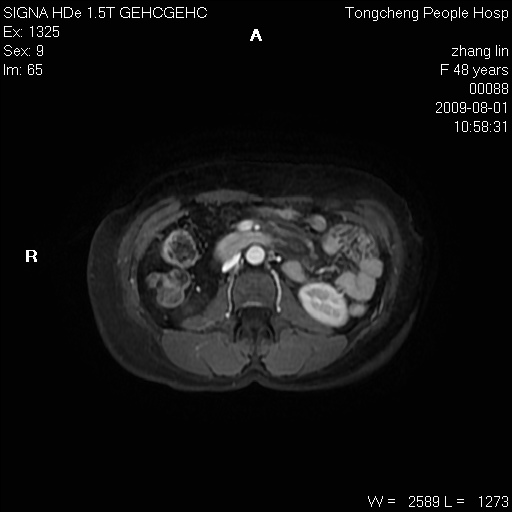

女,48岁。健康体检,彩超发现右肾占位性病变。平素健康。

临床诊断:右肾占位性病变,性质待定(囊肿?肿瘤?)。

上中腹部mr平扫+增强扫描,图像如下:

右肾上极见一类圆形病灶,t1wi呈等信号t2wi呈等高混杂信号,三期增强无强化,边界清---考虑囊肿出血。

同反相位均表现为等信号,病变无强化,考虑含蛋白的囊肿可能,弥散加权相或许有些帮助,

慢性胆囊炎